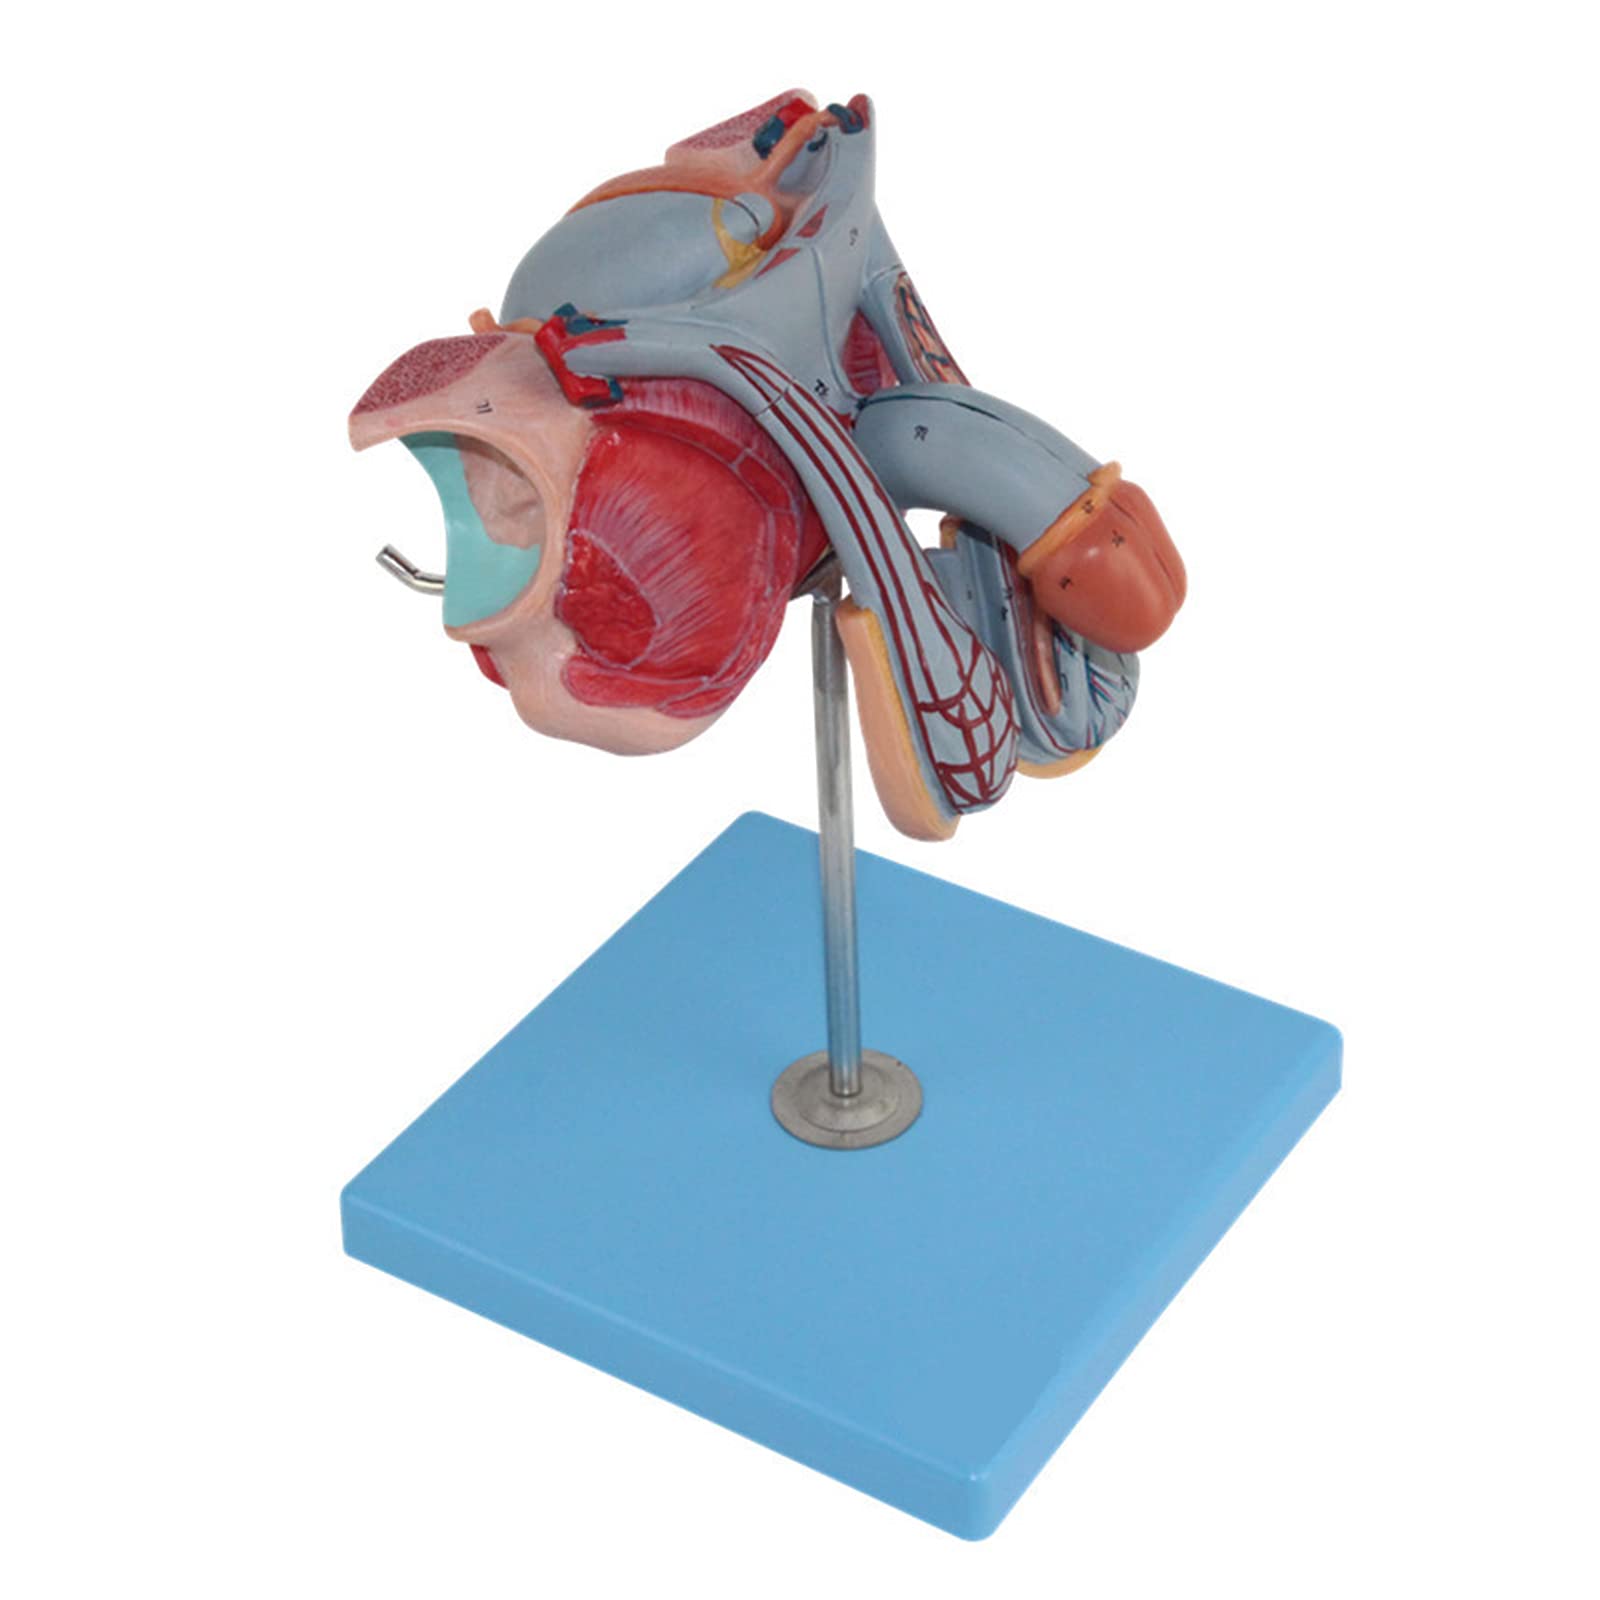

The Male Reproductive Model is a meticulously crafted anatomical aid featuring five detailed parts, including male genital organs and bladder sections. Made from durable, eco-friendly PVC, this model is designed for educational excellence, making it an ideal tool for schools and hospitals to enhance understanding of human anatomy.